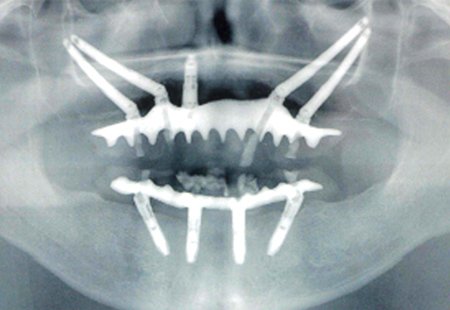

ザイゴマインプラント Zygoma Implants

ザイゴマインプラントは、骨が不足している上顎に対して頬骨(ザイゴマ)を利用して固定する手法で、骨移植を行わずに治療が可能になる場合があります。これにより、従来は手術が難しいとされていた方にも対応の幅が広がっています。

ザイゴマインプラントは、標準的なインプラントより長いインプラント体を使用し、顎骨ではなく頬骨下側に固定することで、上顎にほとんど骨がない場合や骨が極端に薄いケースにも対応できる選択肢として注目されています。この手法では、手術当日に仮歯を装着し、すぐに噛む機能を回復できるよう設計されています。

通常、ザイゴマインプラントは上顎の後方部分に埋入されます。さらに、骨吸収が特に重度の場合には、両側に2本ずつザイゴマインプラントを埋入することもあります。これにより、従来は治療が難しかった症例でも、安定した咬合と審美性を実現できます。